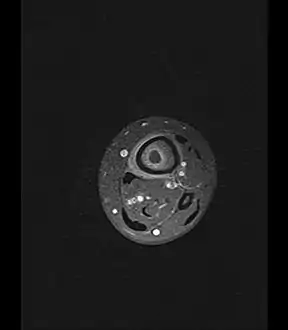

- Axial T1-weighted MRI pre-contrast enhancement showing that the intramedullary collection is T1-hyperintense suggesting proteinaceous viscous fluid consistent with infection.

- Axial T1-weighted fat-saturated MRI image following IV gadolinium contrast demonstrating the intramedullary lytic area seen on radiography to be ring enhancing consistent with a purulent fluid collection. Extensive circumferential periosteal enhancement is noted. There is also substantial bone marrow enhancement.